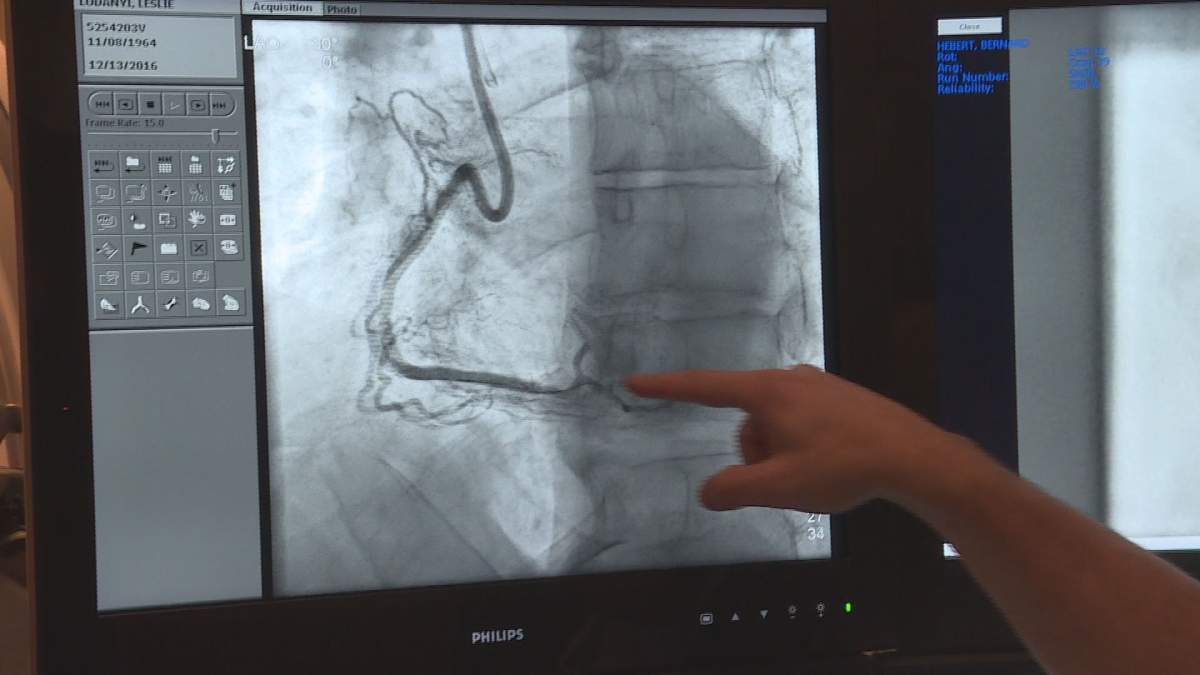

The MUHC became the first hospital to operate on a patient with clogged arteries with a new technology called TrapLiner. Dec. 13, 2016. Max Kalinowicz/Global News